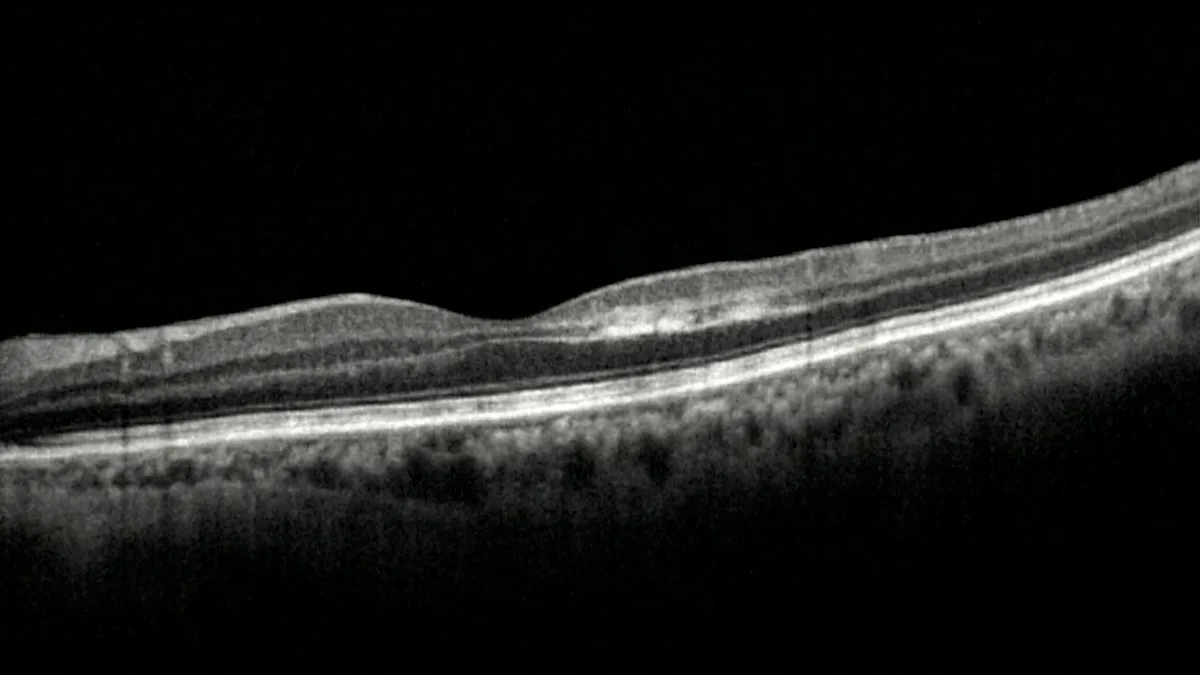

OCT:诊断的关键检查

OCT(光学相干断层扫描)是确诊旁中心急性中层黄斑病变不可或缺的检查。其特征性表现为视网膜内核层和内丛状层的带状高反射,对应于这些层细胞的缺血和细胞毒性水肿。在晚期阶段,这种高反射信号演变为内核层的变薄和萎缩,反映不可逆的细胞丧失(萨拉夫等,《视网膜》,2013年)。

OCT血管造影:深层丛的可视化

OCT血管造影是理解旁中心急性中层黄斑病变的重大进展。这项无创检查无需注射造影剂,可直接显示暗点对应区域深层毛细血管丛血流减少的情况。OCT血管造影因此证实了深层缺血机制,并有助于将旁中心急性中层黄斑病变与其他黄斑疾病进行鉴别(内米罗夫等,《视网膜》,2016年)。